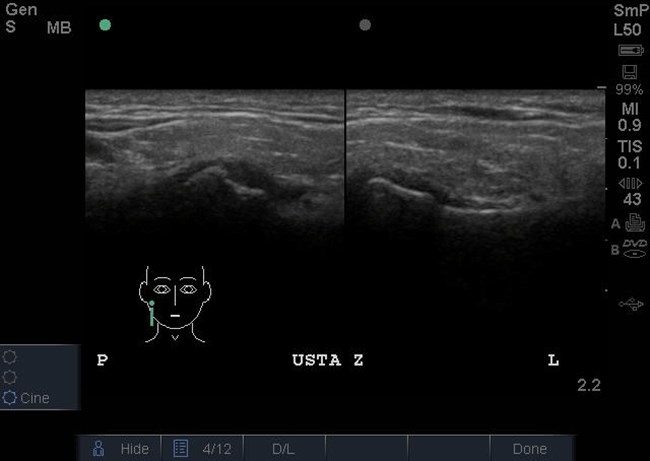

Następnie wykonano badanie ultrasonograficzne (USG) w celu oceny funkcji krążka stawowego ssż oraz mięśni narządu żucia. W prawym stawie skroniowo-żuchwowym stwierdzono doprzednie przemieszczenie krążka stawowego w zwarciu, które utrzymywało się w rozwarciu (ryc. 3 i 4). W lewym stawie skroniowo-żuchwowym krążek stawowy był położony na szczycie głowy żuchwy w zwarciu i rozwarciu (ryc. 3 i 4). Nie stwierdzono przerostu mięśni żwaczy ani patologii w obrębie mięśni mostkowo-obojczykowo-sutkowych, jak też powiększonych regionalnych węzłów chłonnych.

Ryc. 3. Przekroje strzałkowe ssż w zwarciu w badaniu USG. Widoczne doprzednie przemieszczenie krążka stawowego w prawym ssż. W lewym ssż krążek stawowy jest położony na szczycie głowy żuchwy.

Ryc. 4. Przekroje strzałkowe ssż w rozwarciu w badaniu USG. Utrzymuje się doprzednie przemieszczenie krążka w prawym ssż. W lewym ssż krążek znajduje się na szczycie guzka.